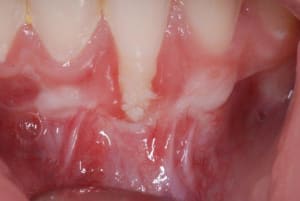

12_jours_post-op_yq86sa.jpg